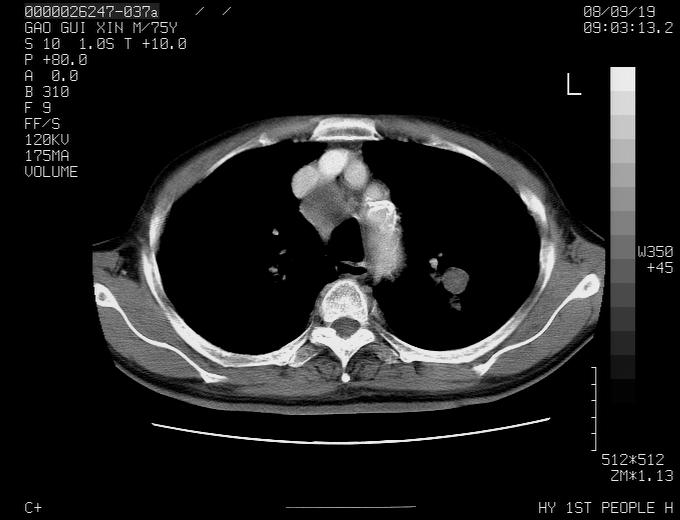

感谢各位老师的意见,左上肺病灶,我本人趋向结核,原因:左上肺见两个类圆形结节,仔细回顾4月份ct似乎原片在该处有条片状密度增高影,强化不明显。

现上传增强片,请各位老师仔细帮我看一下。

右上肺可见条索状影,并可见钙化,左上肺结节可以考虑为结核球,但气管前腔静脉后有肿大淋巴结,本人觉得左上肺结节不能排除转移瘤的可能,右上肺为陈旧性结核灶。

左肺上叶周围性肺癌并纵隔多组lnm.不可能是tb.

左肺上叶尖段瘢痕癌并纵隔淋巴结转移解释更好一些.

左肺周围癌并纵隔淋巴结转移,另一小结节是血管影

1)左肺上叶尖段周围型肺癌并纵隔淋巴结转移。2)冠状动脉及主动脉钙化。